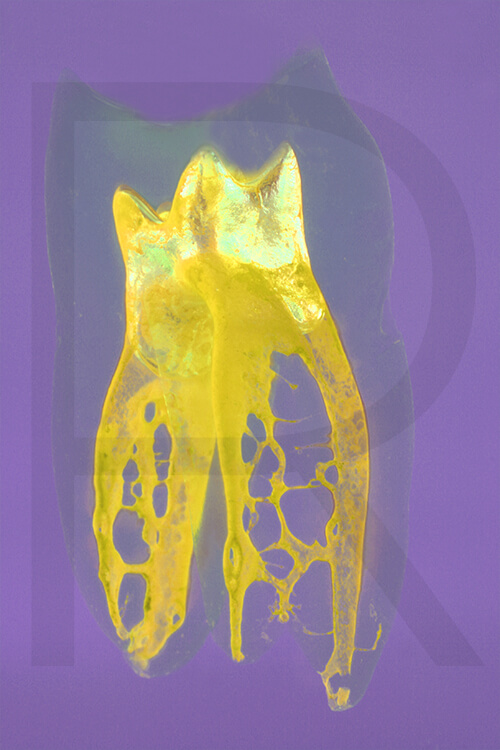

Bildauswahl Pop Art

- Foto hinter 3mm Acrylglas, rahmenlos

- hochwertige, unsichtbare Aufhängung, "schwebend“

- Hoher UV-Schutz für lang anhaltend strahlende Farben

- Bruchsicher und leichter als Glas

- Beeindruckende Farben und brilliante Tiefenwirkung

- Druck erfolgt ohne Wasserzeichen

- Bildgröße Variante 1: 90 x 120 cm

- Preis auf Anfrage, zuzüglich 20,90 Euro Versand & Porto innerhalb Deutschlands, weiterer Versand auf Anfrage

- Bildgröße Variante 2: 90 x 90 cm, quadratisch

- Preis auf Anfrage, zuzüglich 20,90 Euro Versand & Porto innerhalb Deutschlands, weiterer Versand auf Anfrage

- Bildgröße Variante 3: 60 x 120 cm, Hochformat

Preis auf Anfrage, zuzüglich 20,90 Euro Versand & Porto innerhalb Deutschlands, weiterer Versand auf Anfrage

Wenn Sie Interesse an den Fotos transparenter Zahnpräparate haben, bieten wir hier die Möglichkeit einige Versionen als Acrylbilder (alle Detailinformationen zu Größe und Preis siehe obige Auswahl) zu bestellen.

Die Bilder sind nicht nur zur Praxisverschönerung geeignet sondern auch eine wertvolle Unterstützung bei der Patientenberatung vor endodontischen Behandlungen.